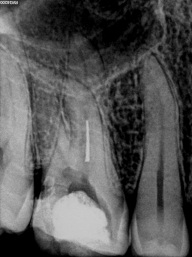

O instrumento Ultrassônico específico escolhido deve ter um comprimento que alcance a obstrução e um diâmetro pequeno o bastante para fornecer visão direta no instrumento fraturado. Esta ponta de inserção é colocada contra a cabeça do seguimento fraturado no interior do canal, ativada e movida na direção anti-horária em torno da obstrução. Esse trabalho ultra-sônico utiliza o Stropko Irrigador (stropko.com) com uma cânula luer-lock de 29 ga(Ultradent Producs) para fornecer uma corrente contolada de ar, que serve para soprar a apoeira dentinária e manter a visão contínua.

O objetivo deste método ultra-sônico é trefinar, lixar a dentina e expor 2 a 3 mm do aspecto mais coronário da obstrução, ou cerca de um terço de seu comprimento total. Algumas gotas de uma solução de 17% de EDTA são pingadas no canal e servem como um adjuvante de remoção potente ao colocar uma ponta energizada contra a cabeça de um segmento de lima quebrado. Clinicamente, depois de criar uma plataforma de preparo e expor a cabeça de um segmento de lima quebrado, colocar gentilmente a ponta energizada entre a lima afunilada e a parede do canal afunilado muitas vezes faz com que o instrumento quebrado se solte, desenrosque e saia do canal. No entanto, procedimentos ultra-sônicos podem não ser bem-sucedidos e, nesses casos, um método de remoção secundária será necessário.